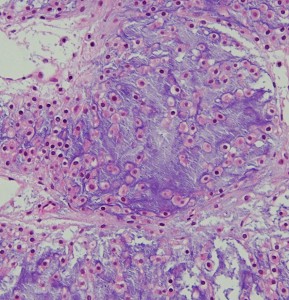

病理

低悪性度軟骨肉腫の病理像 grade 2 chondrosarcoma

背景は好塩基性の軟骨基質(粘液状 myxoid,軟骨様 chondroid)です。好酸性胞体をもつ異型紡錘形ないし上皮様細胞が多結節状に増殖しています。細胞密度はやや高い部分もあり,核は濃縮され大小不同や2核の細胞も見られます。MIB-1 index 3%